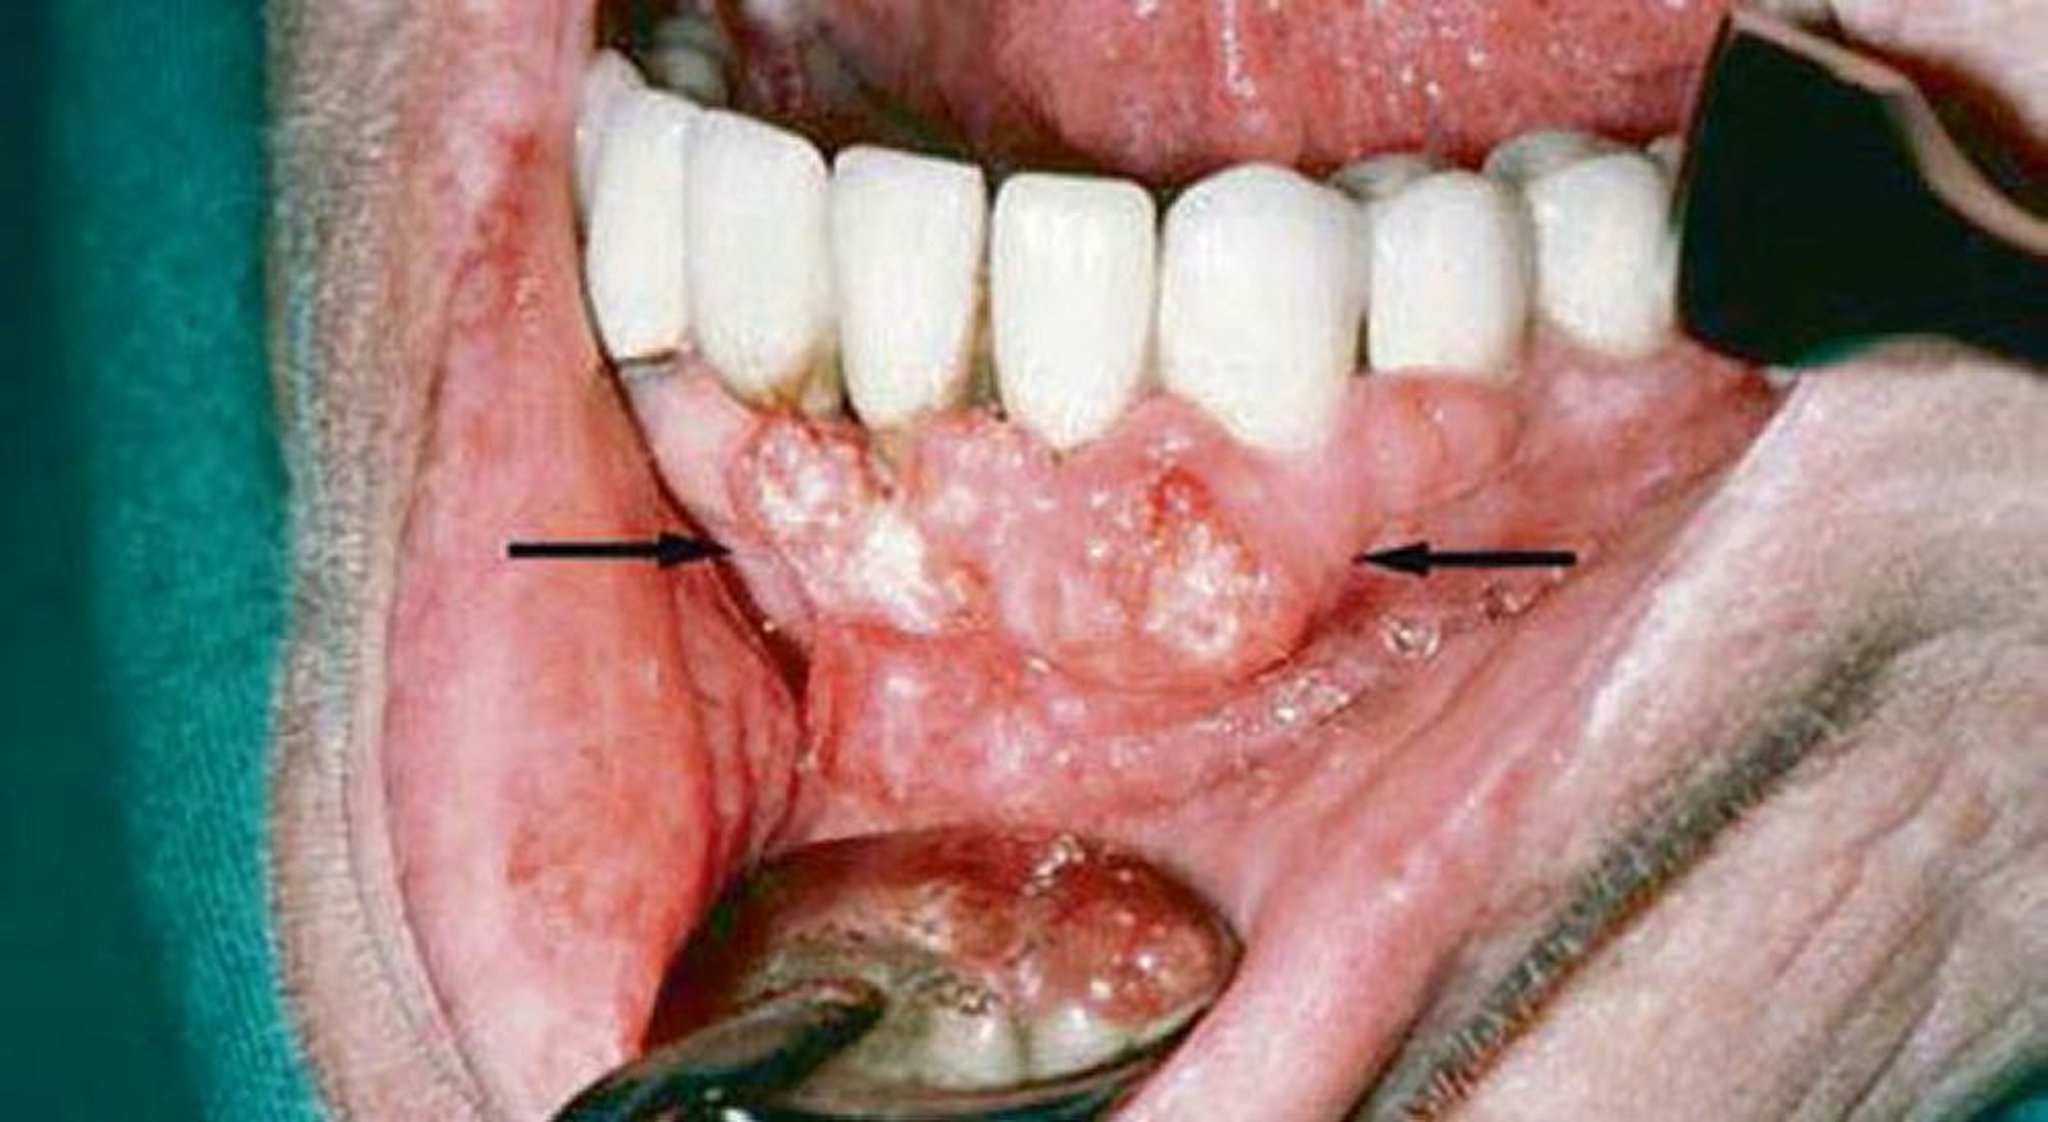

Carcinoma squamocellulare (lesioni gengivali)

L'esame gengivale di questo paziente ha mostrato evidenza di carcinoma a cellule squamose. Gli studi di imaging hanno mostrato l'invasione della mandibola.